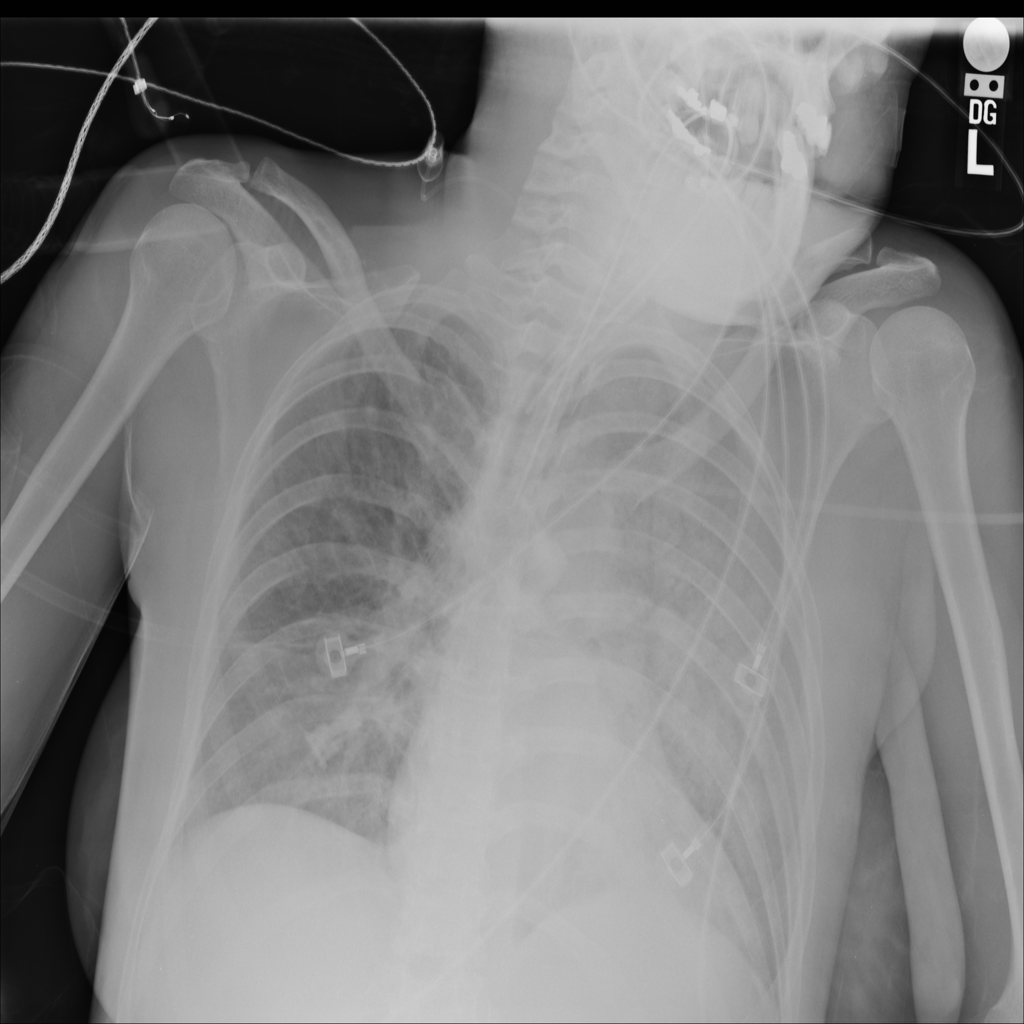

PAT-E828 · IMG-004Edema

PAT-E828 · IMG-004

AP